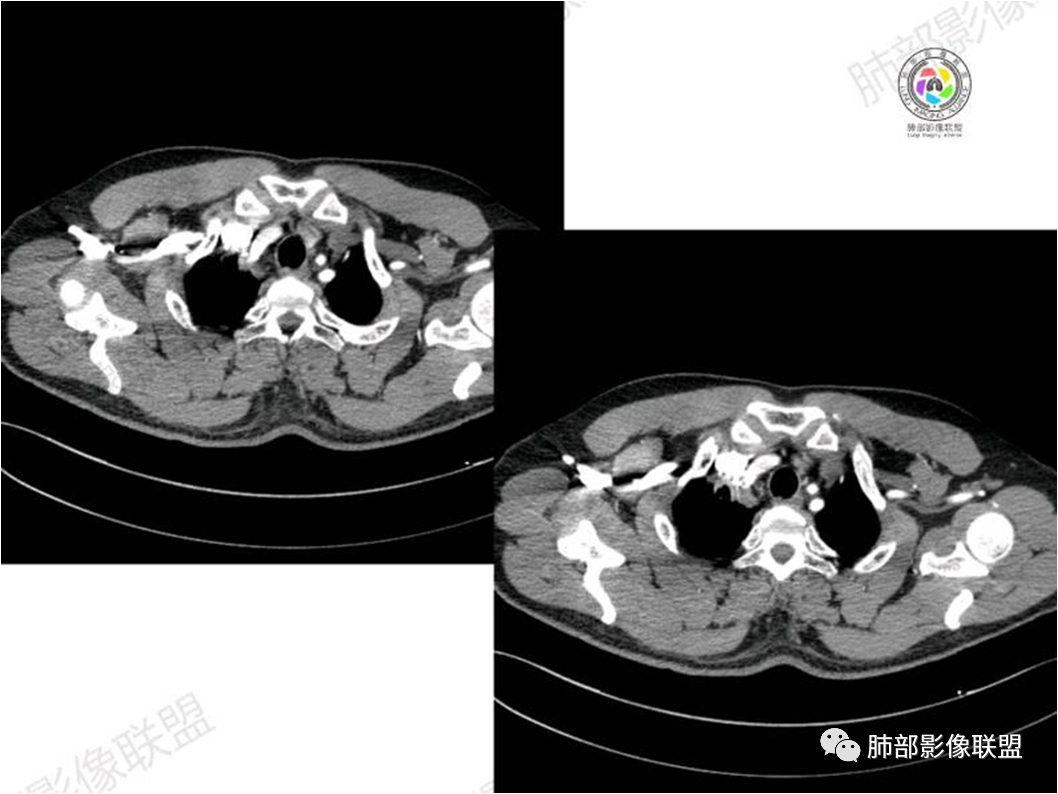

胸部CT:

黏膜相关淋巴组织(Mucosa associated lymphoid tissue, MALT)淋巴瘤是来源于黏膜相关淋巴 组织边缘带的低度恶性非霍奇金B细胞淋巴瘤。肺MALT淋巴瘤较为罕见,约占淋巴瘤的0.14%~1%,易被误诊为肺炎或肺癌。

MALT淋巴瘤这一概念最早由Isaacson和 Wright等于1983年提出,其可发生全身具有黏膜的器官或组织,最常见于胃肠道,其次为肺(15%)组织,病因不明,目前多认为与慢性感染、吸烟或自身免疫性疾病有关。肺MALT淋巴瘤是较为罕见的低度恶性肿瘤,多见于50-70岁,男女发病率无明显差异,或男性略多于女性。

MALT淋巴瘤影像表现为实变、结节及磨玻璃影,其中实变是其特点,胸膜下或支气管血管束节段性分布具有特征性,跨叶征较常见,这可能与肿瘤细胞进入血循环后往往又回到上皮黏膜部位,它们从一处黏膜到另一处黏膜,但不会到外周淋巴组织等有关。国外多名学者的影像-病理研究报道认为其病理学基础是由于肿瘤细胞沿支气管血管束周围间质及胸膜浸润生长,形成小叶间隔增厚、支气管血管束增粗等间质性改变,进一步浸润肺泡壁、充填肺泡腔。

⑥肺门及纵隔淋巴结肿大少见;

⑧邻近胸膜多无增厚,部分胸膜下见清晰脂肪或少许积液可能具有一定特征性,既往国内外研究尚未报道此征象,本文认为其病理学基础可能为肿瘤细胞生长缓慢,多为间质淋巴瘤样浸润而不破坏脏器解剖结构,肺泡塌陷及周围纤维组织增生,可能致病灶牵拉邻近胸膜有关,这不同于文献;报道的机化性肺炎致邻近胸膜多条状水肿、增厚,此征象有助于二者的鉴别。